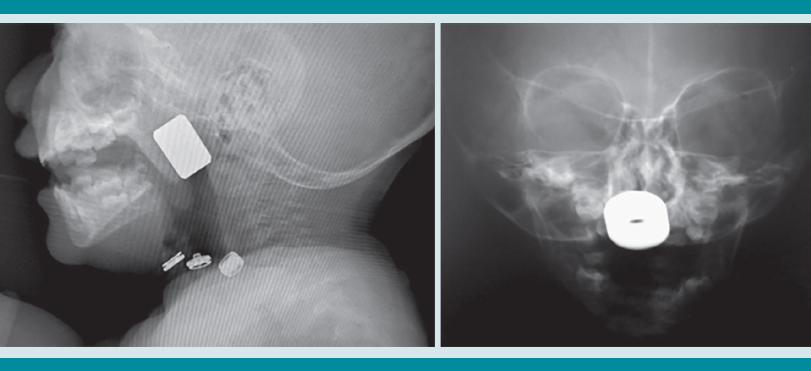

La radiografía de tórax es el primer estudio en un paciente pediátrico que llega al servicio de urgencias con sospecha de aspiración de cuerpo extraño. Gran parte de los objetos aspirados son radiolúcidos (biológicos y plásticos) y, por lo tanto, no se ven por este medio. Solo se logrará observar el cuerpo extraño en 15% de los casos (metálicos y huesos).1,6,8 Es más común identificar datos indirectos (aparecen hasta en 50% de las radiografías), que son consecuencia de la obstrucción en la vía aérea (atrapamiento de aire, atelectasias, consolidación, neumotórax) (Figuras 1,2,3,4,5). Respecto de las radiografías de tórax es que, incluso 45% pueden interpretarse normales, lo que puede resultar en un diagnóstico erróneo.1,6,9

Si al momento de consultar el paciente se encuentra en la etapa aguda, pero está estable, es decir, sin datos clínicos de inestabilidad cardiorrespiratoria, o se encuentra en la etapa oligosintomática pueden solicitarse los estudios de imagen. La radiografía de tórax es el principal recurso con el que cuentan la mayor parte de los servicios de urgencias. Es rápido, fácil, poco costoso y no requiere sedación. En caso de que sea un objeto radio-opaco, aportará el diagnóstico de manera rápida, y dará la localización del objeto (Figura 7). En caso de ser radiolúcido, la radiografía puede ser normal o mostrar los datos indirectos de obstrucción comentados. La tomografía axial computada de tórax puede considerarse si se cuenta con el recurso, tomando en cuenta lo mencionado.